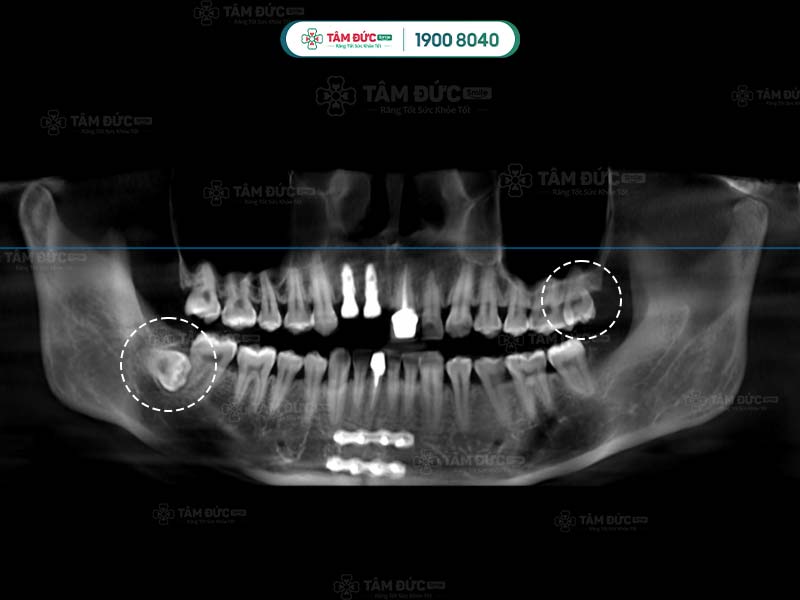

Răng khôn qua phim chụp X-Quang

Hình dạng của chân răng khôn hay còn gọi là gốc răng khôn ở mỗi người có sự khác biệt. Răng khôn có hình dáng khác với những chiếc răng còn lại, chúng hầu như có từ 2, 3 thậm chí là 4 gốc răng. Các chân này thường hợp nhất với nhau tạo thành chân lớn. Tuy nhiên, một số khác lại cuộn tròn hoặc xòe ra các hướng khác nhau.

Một số trường hợp đặc biệt, răng khôn có thể có nhiều hơn 4 chân răng. Chính vì thế, việc biết được răng khôn có mấy chân là điều cần thiết giúp bác sĩ lựa chọn giải pháp nhổ răng khôn an toàn nhất.

Chân của răng khôn có thể xòe nhiều hướng với nhiều hình thái khác nhau. Ngoài ra, việc răng khôn mọc ngầm cũng tiềm ẩn nhiều nguy hiểm. Nếu để thời gian lâu dài, chân răng khôn mọc ngầm hoặc lệch có thể ảnh hưởng đến các dây thần kinh xung quanh.

Đầu tiên là bước thăm khám lâm sàng để thu thập những chỉ số cần thiết như: chỉ số đông máu, số lượng tiểu cầu… Tiếp đến, Quý khách sẽ được chụp X-quang nhằm xác định răng khôn có mấy chân và hình dáng của chân răng khôn.

Sau khi nhận kết quả chụp phim, bác sĩ tiến hành đánh giá tình trạng và độ khó của phẫu thuật. Tiếp đến, Quý khách sẽ được tiêm thuốc gây tê tại chỗ. Với trường hợp răng khôn dễ nhổ: bác sĩ tiến hành rạch trên nướu, làm sạch vùng phẫu thuật để tiếp cận và nhổ bỏ răng khôn. Trường hợp khó hơn: răng khôn có nhiều chân thì cuộc phẫu thuật có thể kéo dài. Lúc này bác sĩ sẽ rạch và cắt từng chân của răng khôn để đảm bảo an toàn.